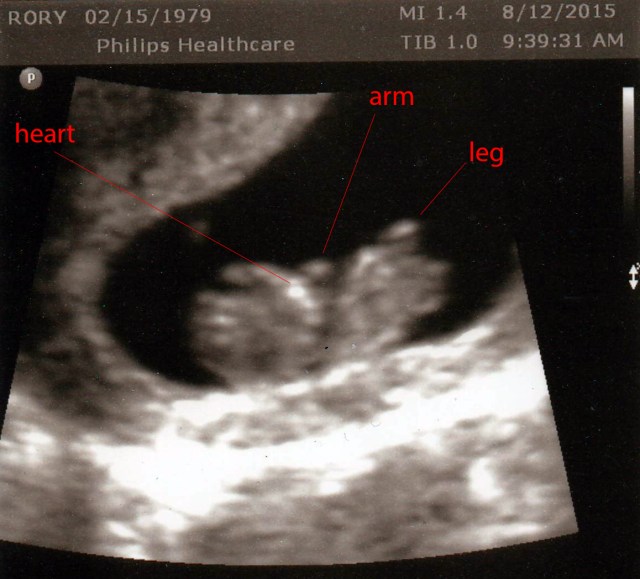

The ultrasound was amaaaaazing. It took about 15 minutes and was sooooo much better than my first ultrasound. The technician would press my belly hard with the ultrasound and you’d see the baby put it’s hands up like “Stop!” And I got to see all sorts of different angles – at one point it was an overhead view and I could actually see the outline of the brain. THE BRAIN! WTH! It was just so crazy. I posted a snippet to my instagram, if you care to watch (link is in the right panel).

No news on the gender front. I had hoped she would be able to see something, but she was quite emphatic that 13 weeks they don’t even attempt to determine the sex, and she barely even looked between the legs (although there were several between the legs shots and I didn’t see anything). However, she did say “he” and “him” a few times when referring to the baby, which I didn’t even notice until I watched the video later that day. Hopefully she was just speaking generically!